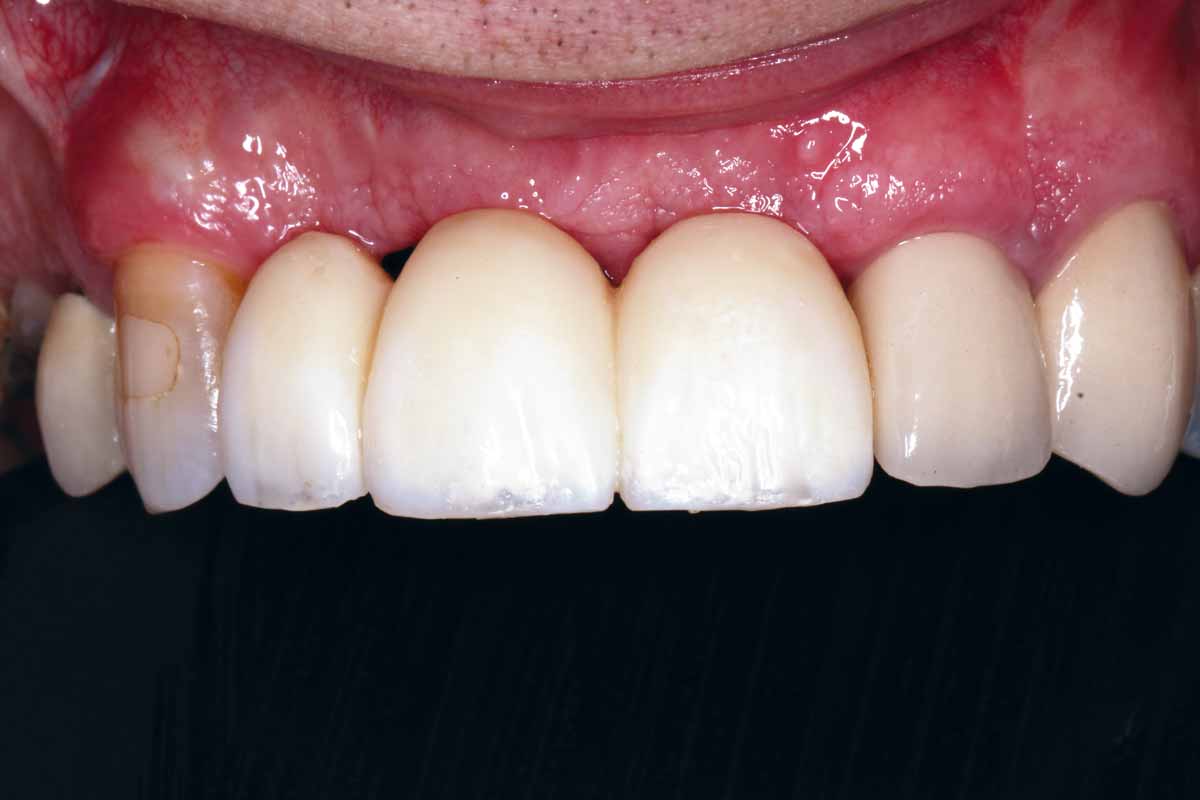

26/27 - Final screw retained restoration 5 months after surgery

GBR and soft tissue augmentation with cerabone® and mucoderm® - H. Maghaireh & V. Ivancheva

27/27 - Final clinical outcome